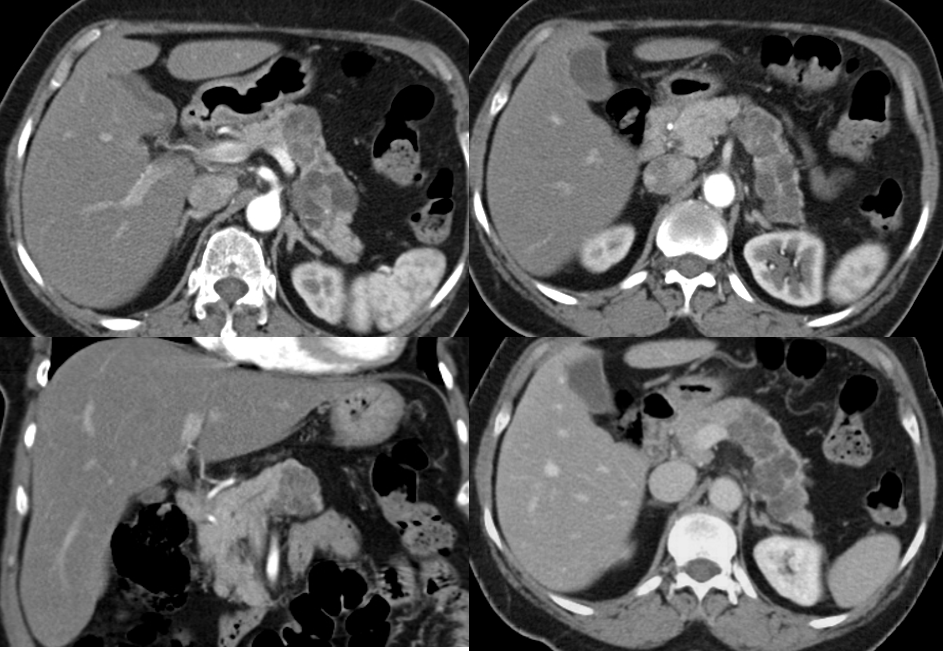

CT scan and MRI can assess the site of the tumor in the pancreas and the evidence of metastases or local invasion by the tumor (staging)

Tumor in the head of pancreas

SMA - Small bowel supply from arrow -